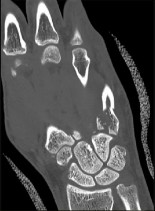

. - الأشعة المقطعية (CT Scan): توفر صوراً تفصيلية ثلاثية الأبعاد للعظام، وهي مفيدة جداً لتقييم الكسور المعقدة، مثل كسور العظم الخطافي (Hamate Hook Fracture) التي قد لا تظهر في الأشعة السينية العادية

، أو لتقييم مدى تدهور العظم في حالات مثل مرض كينبوك. - التصوير بالرنين المغناطيسي (MRI): ممتاز لتقييم الأنسجة الرخوة مثل الأربطة، الأوتار، الأعصاب، والعضلات. يكشف عن التمزقات،